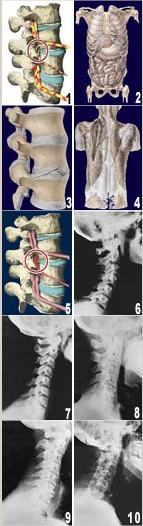

To the right you will see a representation of one type of subluxation. A subluxation, as defined by the Association of Chiropractic Colleges is: "A subluxation is a complex of functional and/or structural and/or pathological articular changes that compromise neural integrity and may influence organ system function and general health." When a subluxation occurs it causes nerve interference in some portion of the body affected by those nerves. The subluxation causes changes to the structure as well as the nerves. These changes get progressively worse as time is allowed to work on the subluxated area of the spine. These changes take the form of ongoing degeneration known as "subluxation degeneration". By understanding the type and amount of changes, it is possible to reasonably estimate the time subluxations have been present in a spine. Having this information is useful in understanding the time and effort needed for correction.

Near Normal

This image is a side x-ray view of the neck. As with all the pictures you will see on this page, the patient is looking to the right of the screen, so you are viewing the right side of their neck. We will call this picture a "near normal" spine. Compare this spine with the ones you will see below on this page. Notice the normal forward curve of the neck. This curve helps absorb shock. Notice how each of the disc spaces between C2 (second bone in neck) and C7 are thick and even, this again is normal. Also notice how the front portions (right on the x-ray) of each of the vertebrae (called the 'body' of the vertebrae) are fairly square with clear and well defined borders. This type of arrangement is normal in the neck. Normal vertebrae in other parts of the spine also have similar characteristics to what we see here. When subluxations occur and are left uncorrected, ongoing relentless changes occur that result in damage to the structure and function of the spine along with nerve damage and the resulting problems caused from improper nerve supply.

Phase One Subluxation Degeneration

Phase One Subluxation Degeneration is seen in subluxations that have been present for up to twenty years. This phase is characterized with a loss or change in the normal curve in the spine. In this image you can see that the normal forward (lordotic) curve is lost. This spine even has developed a reverse curve in the neck. The disc spaces have also begun to exhibit a slight change in shape. One good point is that the bodies of each of the vertebrae (the square part in front) still exhibits clean clear borders. Segmental motion may be abnormal but overall motion is probably not affected. Chiropractic reconstructive care for a phase one can take from 6 to 18 months. More than 80% of people with Phase One Subluxation Degeneration have no pain. Therefore, if left uncorrected, phase one continues to progress with time until it eventually reaches the next phase.

Phase Two Subluxation Degeneration

Phase two subluxation degeneration is normally seen in subluxations that have been present between 20 and 40 years. As you can see in the image to the left, this phase has some of the same characteristics of the previous phase including a loss of normal curvature and position as well as an alteration in segmental motion. In addition, spines with Phase Two Subluxation Degeneration many times show a reduction in the patient's range of motion in that area. X-rays of a phase two begin to show calcium changes or buildup at certain levels of the spine. These changes are sometimes called by many names including spurs and arthritis. Disc spaces between the affected vertebrae are noticeably narrower and may appear to be flattening out. Although most people with Phase Two Subluxation Degeneration may not exhibit any symptoms, some may start to feel stiff or achy. Chiropractic reconstructive care for patients in phase two ranges from 1.5 years to 2.5 years. Again, if Phase Two Subluxation Degeneration is left uncorrected it slowly advances to the next phase.

Phase Three Subluxation Degeneration

Phase Three Subluxation Degeneration is caused by subluxations that have been continuing on for between 40 and 65 years. This phase has all of the attributes of the previous phases, only worse. The curvatures are abnormal, the disc spaces are vastly decreased and changed. This can be seen in this image. Calcium changes on the spine are abundant in this phase. Normally, people in phase three have a restricted range of motion and probably exhibit symptoms of some kind. In phase three the vertebrae show obvious changes and mutations in shape. Projections made of calcium, sometimes referred to as "spurs or lipping", can be readily seen on x-ray. Chiropractic reconstructive care for patients in phase three ranges from 2.5 years to 3.5 years. This does not mean that at the end of this time that any or all of the calcium changes will be gone. In many instances the body adapts to the presence of the calcium and positive changes can only be measured from a functional standpoint. As before, if Phase Three Subluxation Degeneration is left unchecked it slowly advances.

Phase Four Subluxation Degeneration

Phase four subluxation degeneration is seen with subluxations that have been raging on uncorrected or altered for over sixty five years. Phase four is a grave condition that will negatively affect the patients longevity and quality of life. The massive amount of neurological damage caused by years of subluxation that have lead to phase four are probably taking a serious toll on this person's health status. X-rays in phase four show serious severe structural changes. As you can see in this image, vertebrae exhibit massive calcium changes, disc spaces appear blurred, and the bones themselves appear fused. In this scenario the patient will have a severe restriction of range of motion in addition to probably a number of other health issues. Reconstruction may not be possible in phase four, but care can be directed to some reduction in subluxation with the goal of improvement in the quality of life remaining. Patients in Phase Four Subluxation Degeneration have a serious situation both structurally and neurologically, but they are certainly not beyond hope. Many patients in phase four report significant improvements in symptoms, conditions, mobility and quality of life.